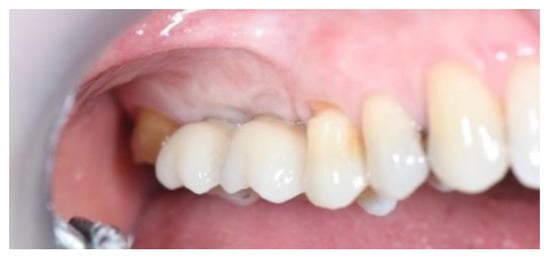

2.2. Follow-Up

3. Results